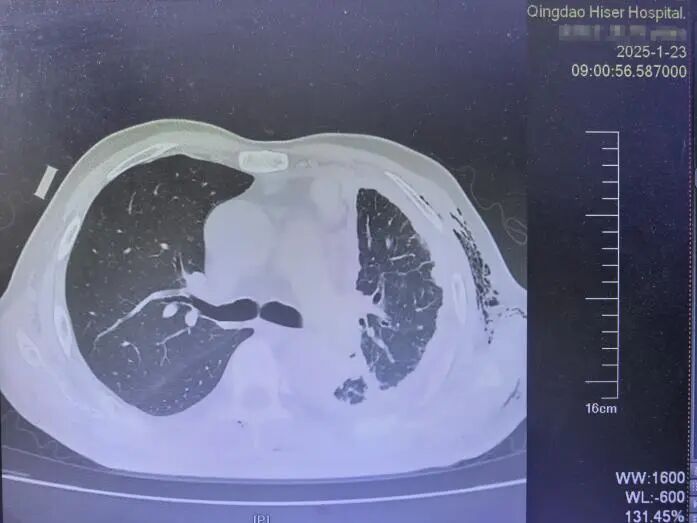

入院后,相關(guān)檢查顯示患者病情極為嚴(yán)重:腫塊幾乎遍布左側(cè)胸膜,并已侵蝕穿透胸膜,到達(dá)胸部腋下軟組織,伴有嚴(yán)重胸水和肺部感染。更糟糕的是,由于患者體質(zhì)虛弱,長(zhǎng)途跋涉后感染了乙流、合胞病毒、腺病毒和肺炎支原體,并出現(xiàn)房顫,一度病情危重。付文勝主任團(tuán)隊(duì)及時(shí)給予了抗病毒、消炎、復(fù)律治療,并結(jié)合辨證論治的中藥湯劑和抗腫瘤中藥粉劑進(jìn)行治療。

因此,長(zhǎng)期接觸石棉或有其他高危因素的人群應(yīng)定期體檢。胸部CT等檢查手段有助于早期發(fā)現(xiàn)胸膜異常變化。早發(fā)現(xiàn)、早診斷、早治療是提高胸膜間皮瘤患者生存率的關(guān)鍵。